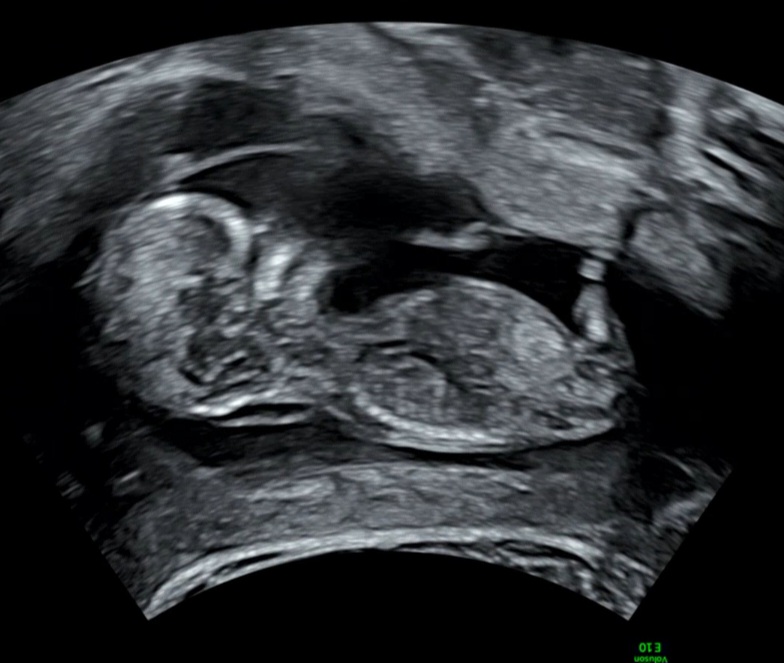

12주 각도법 투표 부탁드려요:-)

12주 5일차 초음파 보고왔는데, 각도법 투표 부탁드려요~~ 빌리ai는 딸 70프로라고 나오네요ㅎㅎ